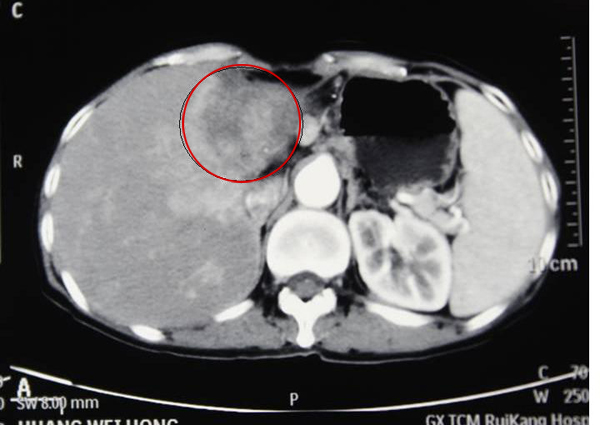

2013年7月,黄阿姨在我院被确诊为肝内胆管细胞癌,肝肿块鸭蛋大。在来我院治疗之前,已经辗转多家医院,病情都没有得到很好的控制。“3年前因为上腹部连腰部剧烈疼痛,到区内一家医院治疗,诊断我是‘肝肿瘤’,经过治疗,疼痛不仅没有缓解反而加剧。之后1年我四处求医,但希望最终都化为泡影,好几次因忍受不了疼痛想放弃治疗,放弃生命,偶然的机会医生介绍我到了瑞康医院。”

2013年7月,黄阿姨在家人的陪同住进了我院。“难受啊,痛的时候想马上死咯!”黄阿姨哽咽着说。因为无外科手术及介入治疗指征,化疗效果不确切,医生建议采取更为先进的射波刀治疗。

治疗前